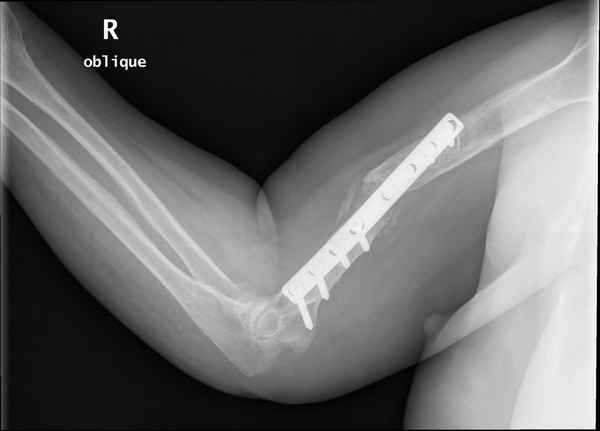

Больная 48 лет, медсестра. Травма получена 7 лет назад, оперирована первично в Турции -

остеосинтез пластиной - несращение - реостеосинтез стержнем там же через год (обычным, с

выстоянеием его в полость плеча) - несращение - поступила к нам впервые в марте 2008 года -

удаление стержня, реостеосинтез пластной и костная пластика, в течение 2 лет лизис кости

вокруг винтов, смещение фиксатора, в марте 2010 - удаление пластины, реостеосинтез

интрамедуллярным стержнем с блокированием (рассверливание + костная пластика).

В динамике - вновь лизис в области перелома, нестабильность дистальных блокирующих винтов.